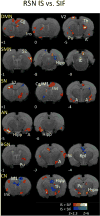

Advances in our understanding of the human pain experience have shifted much of the focus of pain research from the periphery to the brain. Current hypotheses suggest that the progression of migraine depends on abnormal functioning of neurons in multiple brain regions. Accordingly, we sought to capture functional brain changes induced by the application of an inflammatory cocktail known as inflammatory soup (IS), to the dura mater across multiple brain networks. Specifically, we aimed to determine whether IS alters additional neural networks indirectly related to the primary nociceptive pathways via the spinal cord to the thalamus and cortex. IS comprises an acidic combination of bradykinin, serotonin, histamine and prostaglandin PGE2 and was introduced to basic pain research as a tool to activate and sensitize peripheral nociceptors when studying pathological pain conditions associated with allodynia and hyperalgesia. Using this model of intracranial pain, we found that dural application of IS in awake, fully conscious, rats enhanced thalamic, hypothalamic, hippocampal and somatosensory cortex responses to mechanical stimulation of the face (compared to sham synthetic interstitial fluid administration). Furthermore, resting state MRI data revealed altered functional connectivity in a number of networks previously identified in clinical chronic pain populations. These included the default mode, sensorimotor, interoceptive (Salience) and autonomic networks. The findings suggest that activation and sensitization of meningeal nociceptors by IS can enhance the extent to which the brain processes nociceptive signaling, define new level of modulation of affective and cognitive responses to pain; set new tone for hypothalamic regulation of autonomic outflow to the cranium; and change cerebellar functions.